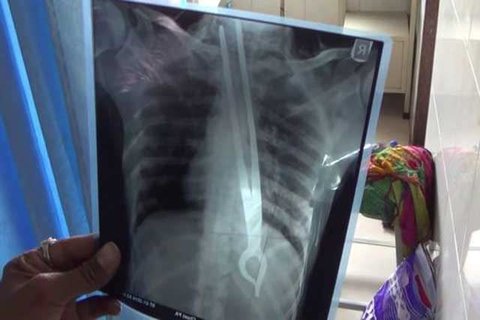

한 남성이 철집게를 삼켜버리고 응급실에 실려왔다는 사고사례

이걸 삼킨 이유는 친구랑 무슨 내기를 했기 때문이라고 한다.

뒤지진 않았지만 뒤지기 전까지 갔다는 모양